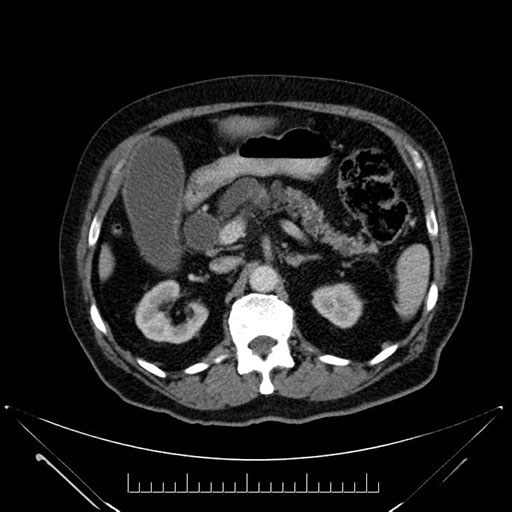

Imaging Analysis

Look through the patient's CT scan to identify any areas of concern for the necessary procedure.

Based on your CT findings, which issue(s) would give reason for "planned slowing down moment(s)" in this case?

Considering a standard Whipple procedure, what step(s) of the operation would you do differently in this case?